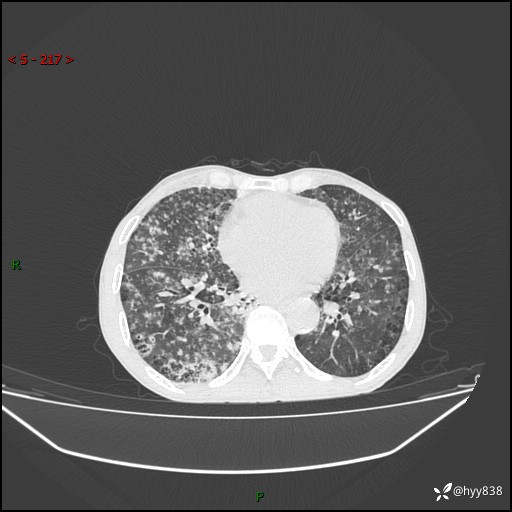

胸部CT平扫